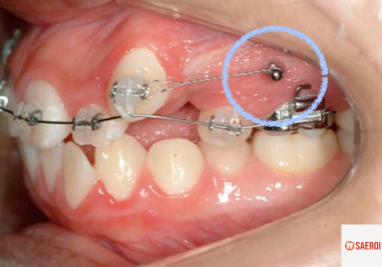

위 사진에서 볼 수 있듯이, 교정용 미니스크류는

우리가 흔히 쓰는 나사와 그 모양이 꽤 비슷합니다.

임플란트와 마찬가지로

티타늄으로 주로 이루어져 있습니다.